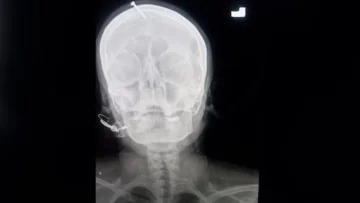

Una radiografía mostró que el clavo había sido clavado cinco centímetros en el cráneo, sin llegar al cerebro.